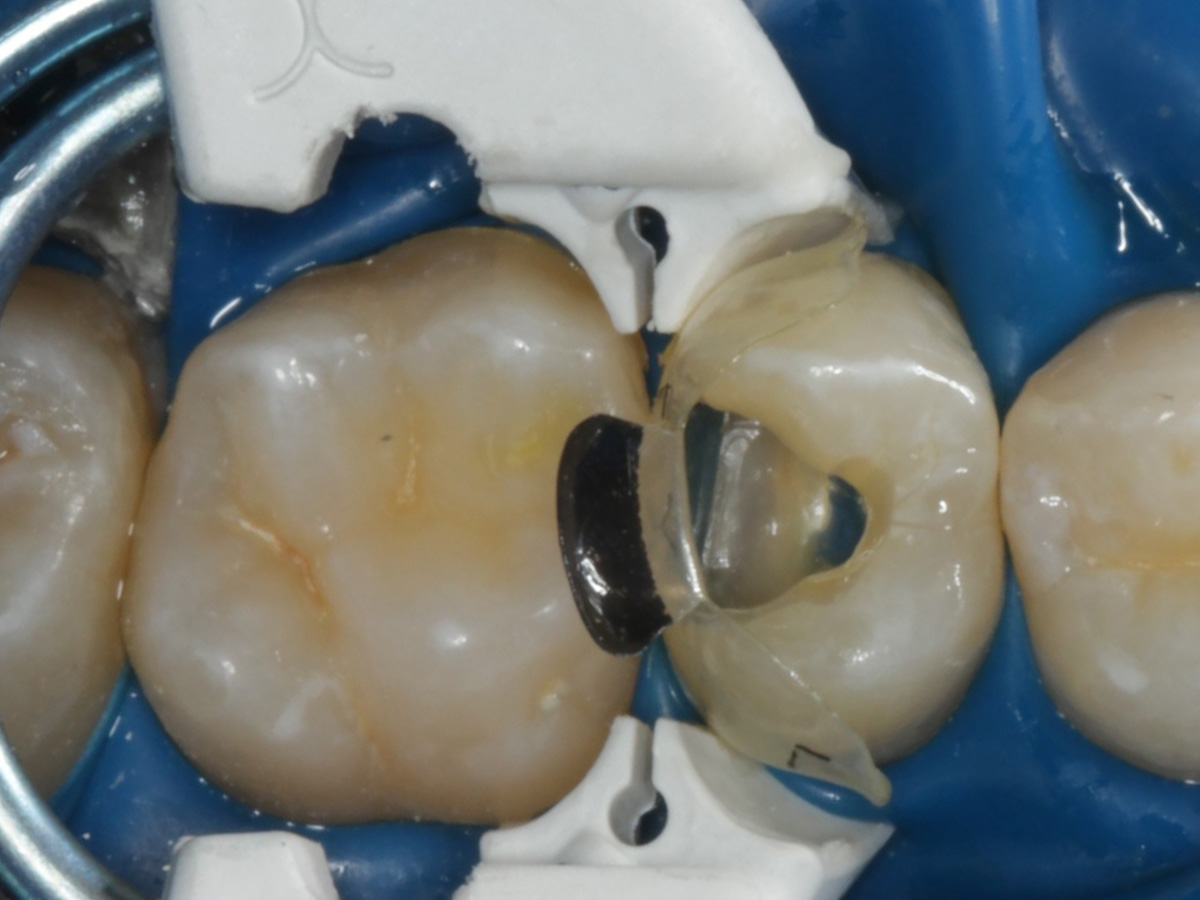

Abbildung 16

Nach Anbringung des Bioclear Twin Ring Universal und Lichthärtung des Einkomponentenadhäsivs

Abbildung 17

Starke Separation der Zähne durch hohe Spannkraft des Twinrings für strammen Kontaktpunkt

Abbildung 18

Bewusst kein Keil zur Vermeidung unerwünschter Matrizenverdrückung